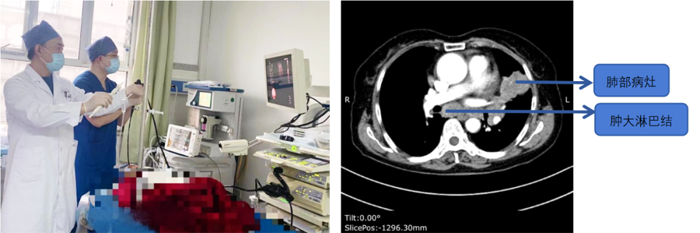

患者,女,72歲,2月來“反復咳嗽、咳痰,偶咳白痰中帶血絲”,胸部CT提示“肺占位、肺炎”,收住院。完善胸部強化CT提示“左肺占位、肺炎、縱膈多發(fā)淋巴結腫大”,電子支氣管鏡檢查見左肺上葉支氣管血塊及壞死物阻塞,清除后見管腔通暢,刷檢DNA細胞學示“細胞退變明顯,建議進一步檢查”。10月27日行CT引導下肺穿刺活檢,病理示“機化性肺炎”,給予抗感染及激素治療,患者癥狀好轉出院。半月前,患者復查肺CT發(fā)現(xiàn)病灶較前稍有增大,張強主任考慮患者癥狀雖有好轉,但仍存在腫瘤性病變可能性。經(jīng)過討論及與患者家屬充分溝通后,決定實施支氣管內超聲引導下針吸活檢術(EBUS-TBNA)+電子支氣管鏡檢查+現(xiàn)場快速評價(ROSE)技術,以提高診斷陽性率。術中ROSE提示查找到可疑癌細胞,取材量較足分。最后病理檢查明確診斷為低分化肺腺癌,隨后進行基因檢測,明確了治療方向。

患者,男,70歲,近2個月來“活動后呼吸困難,近日又出現(xiàn)痰中帶鮮血”,收住院。胸部增強CT見“左肺下葉外周型占位,肺門、縱膈淋巴結腫大”。張強主任帶領團隊討論分析患者病情,高度懷疑為腫瘤性病變,且普通電子支氣管鏡獲取組織困難,病變緊貼主動脈,經(jīng)皮肺穿刺活檢風險大。為明確診斷及分期,決定為患者實施支氣管內超聲引導下針吸活檢術(EBUS-TBNA)+電子支氣管鏡下病灶活檢+現(xiàn)場快速評價(ROSE)。術中ROSE快速診斷查找到肺腺癌細胞,手術過程順利。最后病理檢查明確診斷為肺腺癌,為患者的下一步治療確定了方向。